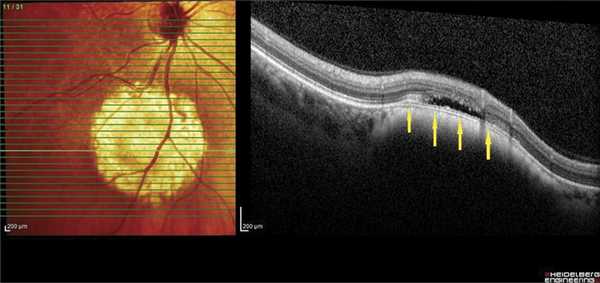

ОНЭ с отеком и дезорганизацией дисков наружных фоторецепторов в макулярной зоне выявлена у 12 больных с ГХ со снижением зрения до 0,02-0,8, проминенцией опухоли 1-4,05 мм и анамнезом заболевания от 1 мес до 15 лет. Наиболее выраженное снижение зрения (до сотых) отмечали в случаях пара- и макулярного расположения ГХ и длительности анамнеза более 10 лет (рис. 5, а), минимальное снижение остроты зрения (до 0,6-0,8) - при длительности анамнеза до 1 года (см. рис. 5, б).

Рис. 5. ОКТ-горизонтальный срез через макулярную зону. а - пациентки Е., Vis OS =0,02, длительность анамнеза 11 лет (ОНЭ, кистозные изменения в макулярной зоне с разрушением фоторецепторов); б - пациентки С., Vis OS =0,7-0,8, длительность анамнеза 6 мес (отечность наружных сегментов фоторецепторов).